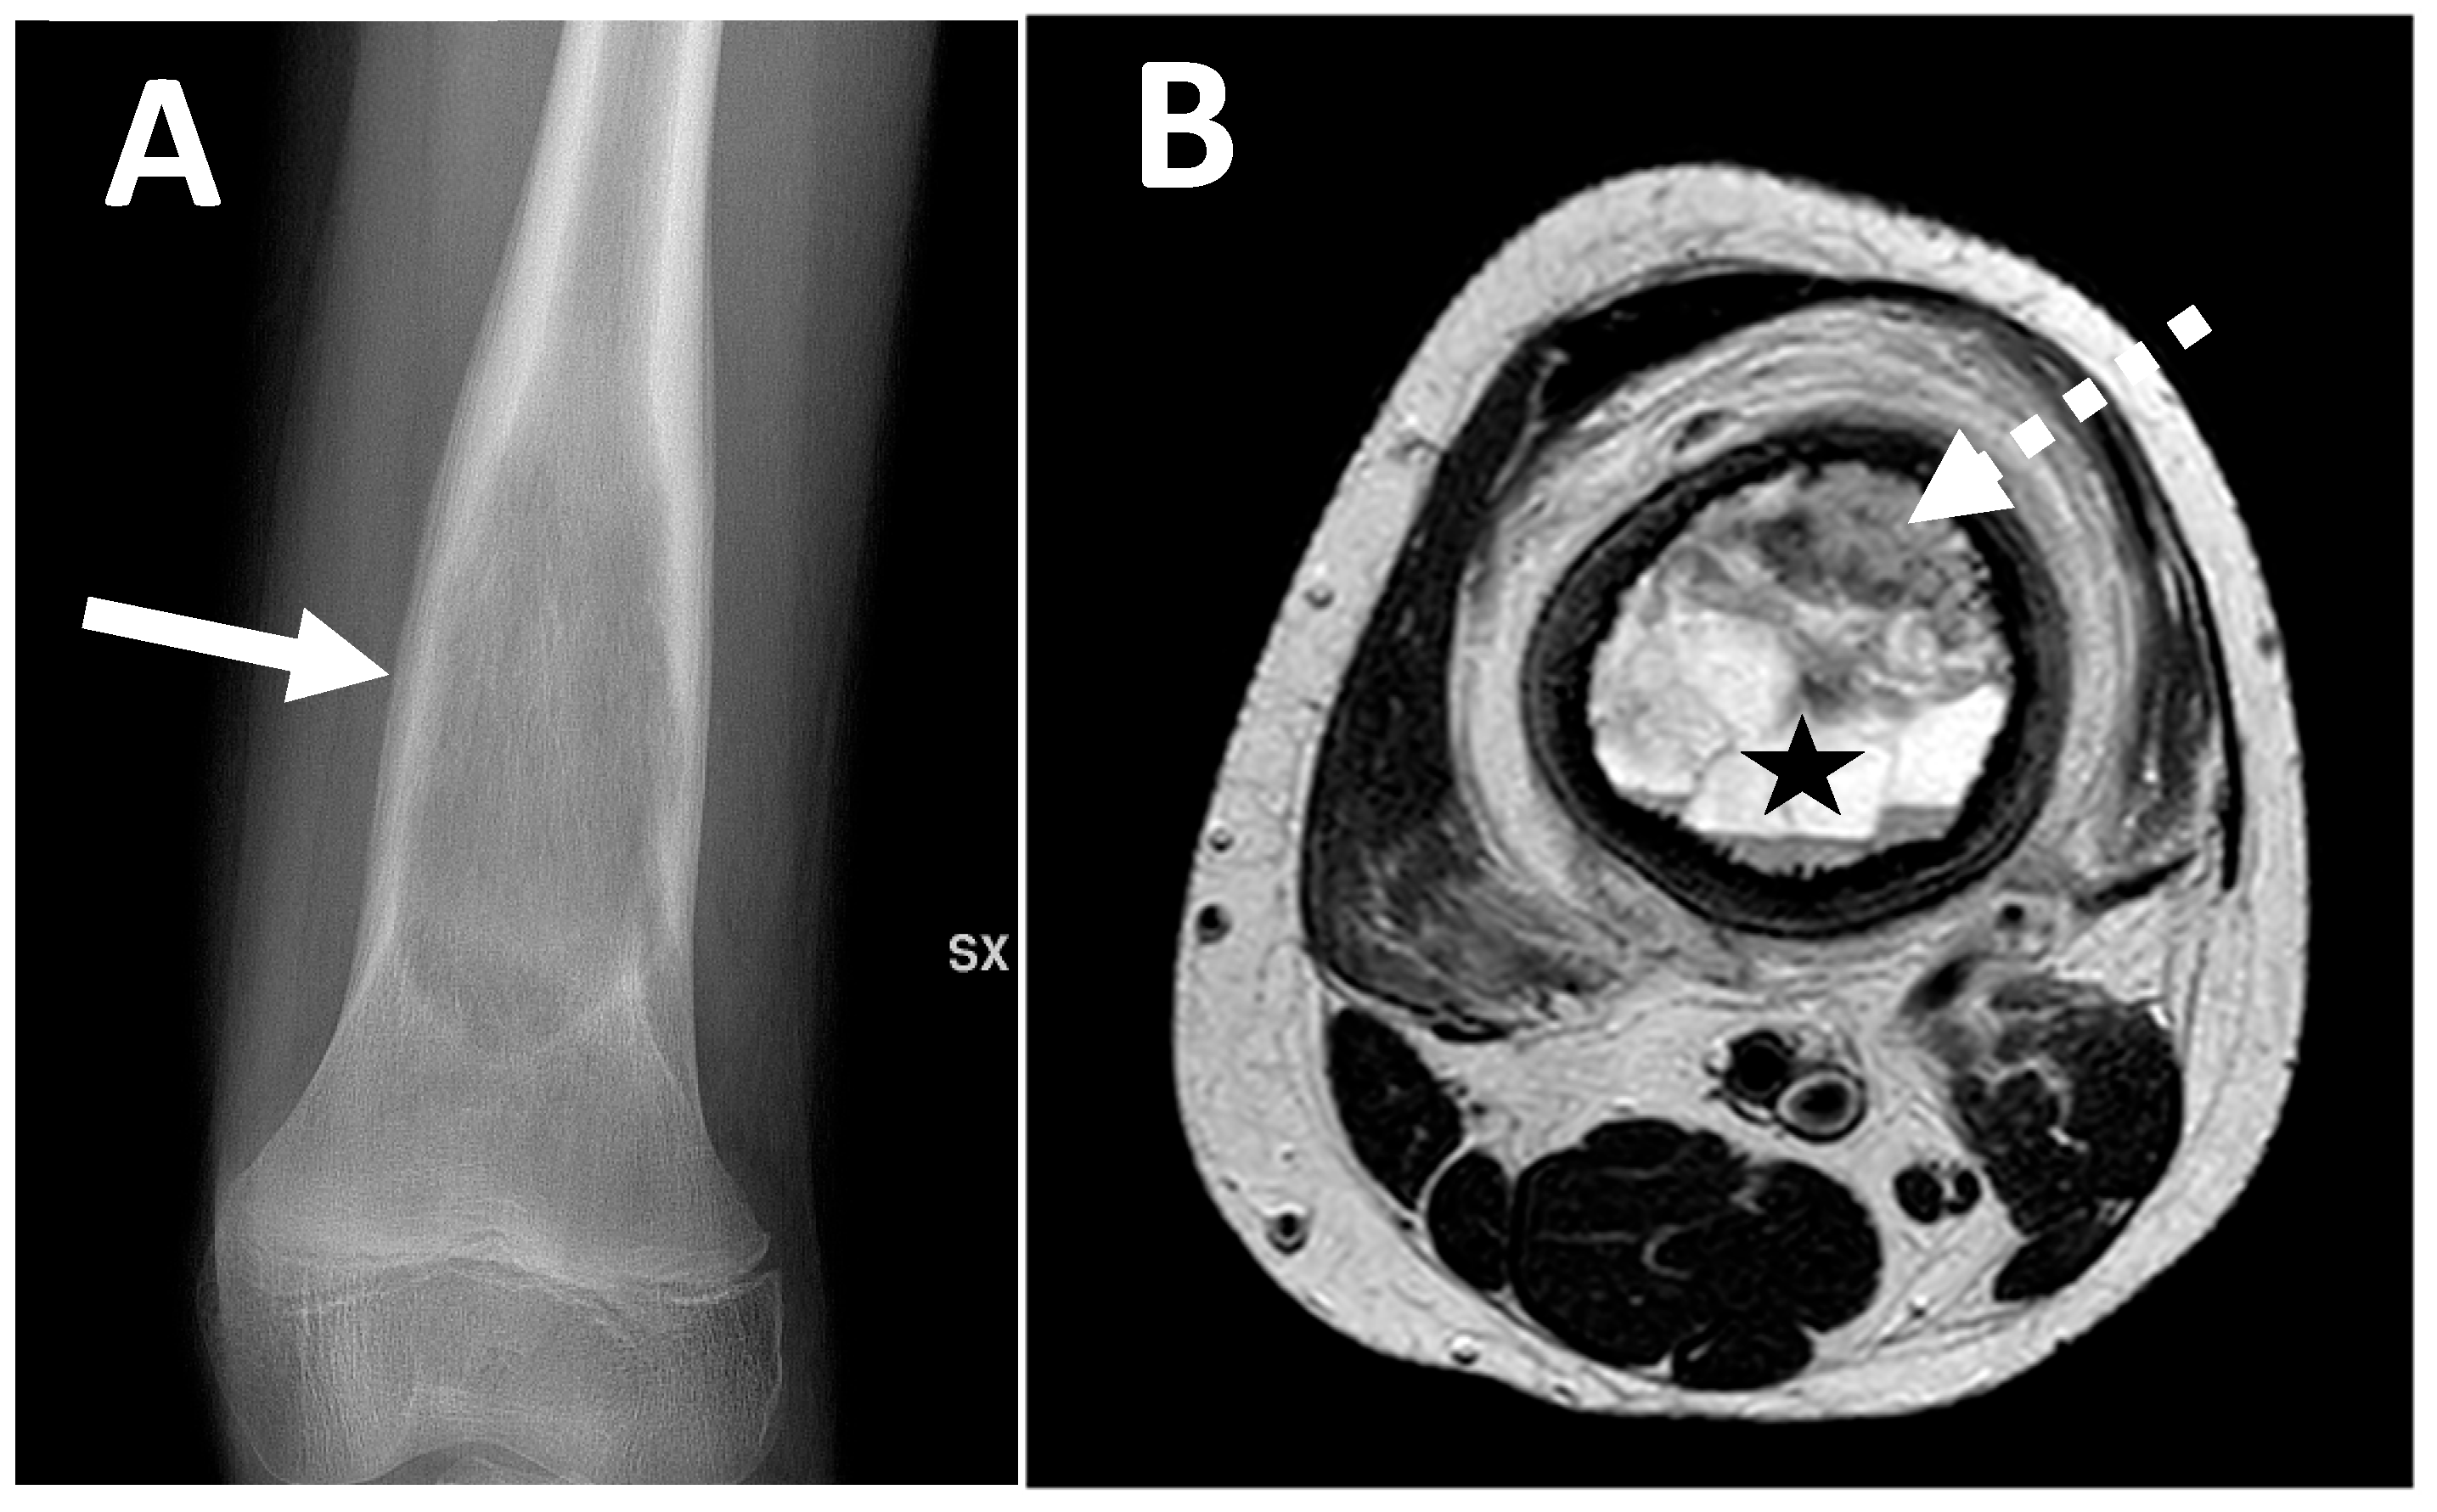

2.2. Radiological Findings on Conventional Radiographs

2.3. Radiological Findings on CT

2.4. Radiological Findings on MRI

| Parosteal | Lobulated osseous mass fused with cortical bone, usually with large dimensions, broad implant base | None, non-aggressive ones, or only cortical thickening | Cauliflower-like mass, thin linear cleavage between portions of tumor and cortical bone, frequent intramedullary involvement |